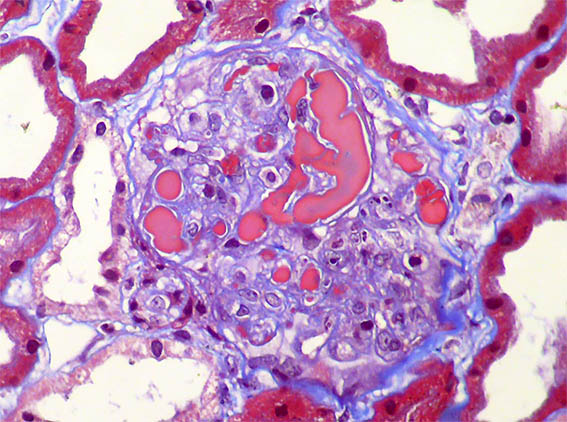

A 62-year-old woman is evaluated for erythema on both legs that has been developing for several weeks. There is no personal pathological history. On physical examination, they found systemic arterial hypertension, edema of the lower limbs, purpuric lesions on both legs, and Raynaud's phenomenon. In paraclinical tests, the hemoleukogram is normal; serum creatinine: 2.1 mg/dL, BUN: 39 mg/dL. ANA, anti-DNA, and ANCA: negative. C3: 82 mg/dL (84-180) and C4: 4.1 mg/dL (12-40). HIV and hepatotropic viruses: negative. In urinalysis there is microhematuria, leukocytes: 5/hpf, proteinuria: 4.2 g/24 hours, with mild hypoalbuminemia.

Figure 5. Masson's trichrome stain, X400.